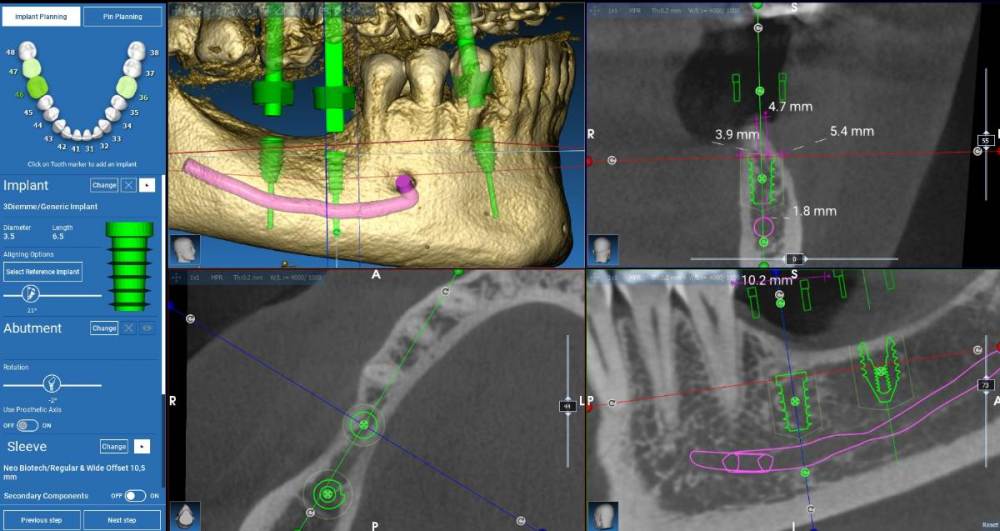

Fin Опубликовано 1 ноября, 2021 Поделиться Опубликовано 1 ноября, 2021 Здравствуйте коллеги. Очень нужно Ваше мнение. Что бы Вы сделали в четвертом сегменте? 1. Анкилос 3.5 х 6.6 в обл. 4.6 и необиотек 4,5(мб 5) на 7.3(0,5). 2. НКР (по ширине) Блоком или титановой сеткой в об 4.6 и после необиотек 4.5 на 7.3( полир шейка пол мм). В области 4.6 тоже что и в первом случае. 3. НКР при помощи спейсера на импланте в области 4.6 (импл 4 на 7,3). В области 4.6 тоже что и в первом случае. 4. Необиотек 4 на 7,3+сст на шейку импл. В области 4.6 тоже что и в первом случае. 5. Ваша вариант. Естественно работа с десной для создания кератинизированной слизистой в всех случаях. Протезирование скорее всего с уровня МЮ. Ссылка на комментарий